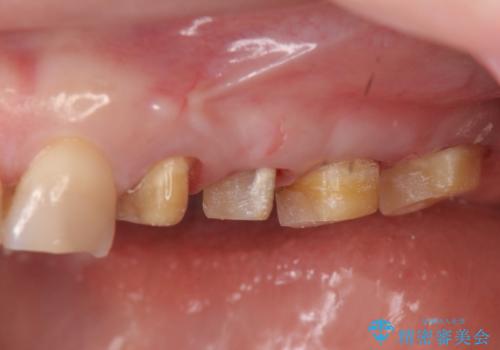

放置した虫歯 根管治療 フルジルコニアクラウン

- 虫歯治療を途中で中断し放置した歯の治療再開を希望され来院されました。

樹脂やクラウン・銀歯の老朽化がみられるため、丁寧に除去を行い根管治療を行ったのち、歯軋り・厚みの少なさを鑑みフルジルコニアクラウンによる補綴を計画します。